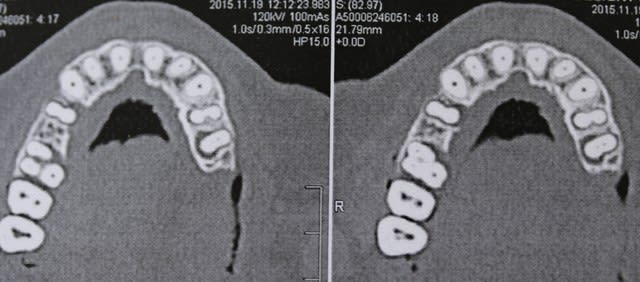

11/12/2015 à 12h29

controle du cas de la page 19 , ce jour .

faut aimer l'aspect champignon , mais ça va , chance !!!!

11.12 - Eugenol

voilà ,j'ai repris la photo de la meme radio , ce qui ne change pas le fait qu'elle soit tjs sur l'arcade :-)

Pc110269 jtiunl - Eugenol